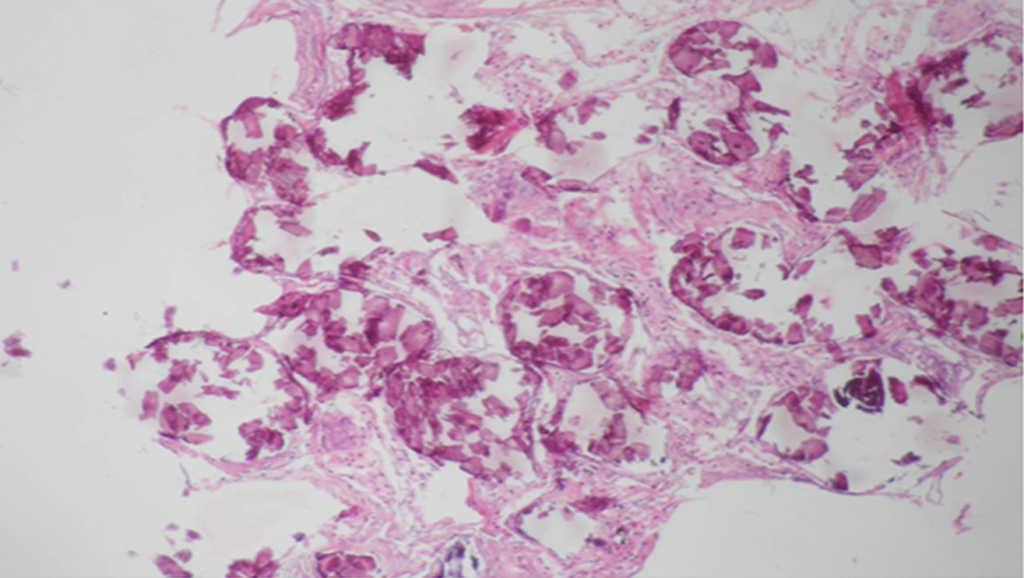

Microlitos alveolares.

Figura 3.

(0,25MB).

Presencia de cuerpos esféricos calcificados (calcosferitas).

Figura 4.

(0,21MB).

En los hallazgos histopatológicos, se encuentran numerosas calcosferitas laminadas, escasa fibrosis de las paredes alveolares y presencia de macrófagos cargados de hemosiderina. Siendo este el reporte de un gran número de casos. El parénquima pulmonar, en la medida que progresa la enfermedad, se degenera causando bulas y fibrosis intersticial. Se describen casos en los que las calcosferitas comprometen las paredes septales, no solo a nivel del espacio alveolar, sino también a nivel bronquial3,22.

Cuando los microlitos se analizan, se observan de forma irregular, redondeados y en ocasiones ovalados, compuestos de láminas con medidas que pueden variar de 0,01 a 0,3mm55, que parecen aumentar en tamaño con la edad hasta ocupar todo el espacio alveolar60 y en estados avanzados entran en contacto con la paredes, dañándolas y siendo estas reemplazadas por tejido fibroso. Los microlitos son compuestos de calcio, fósforo, con concentraciones bajas de hierro, cinc, aluminio y magnesio1,22,61. Su ubicación se da en principio en los lóbulos inferiores, con el trascurrir del tiempo (20 a 30 años), se extienden a todo el pulmón.